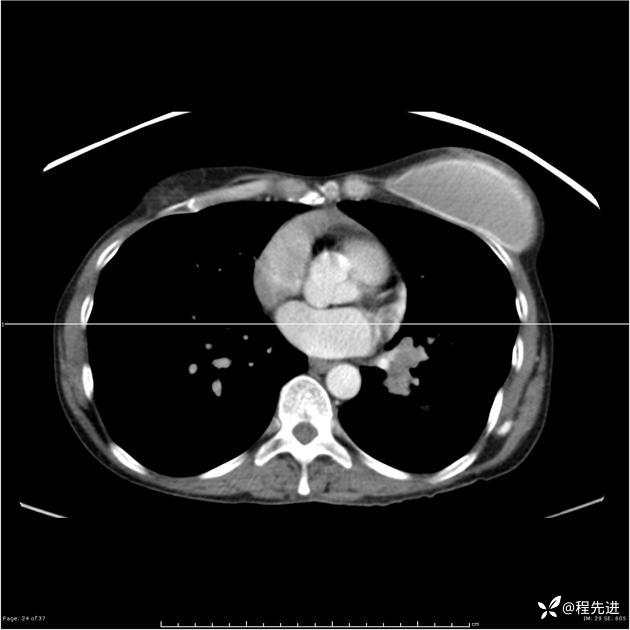

病例女,53岁,气管、左主支气管、下叶支气管内结节,乳头状瘤?期待你的精彩解读

女,53岁

乳头状瘤?